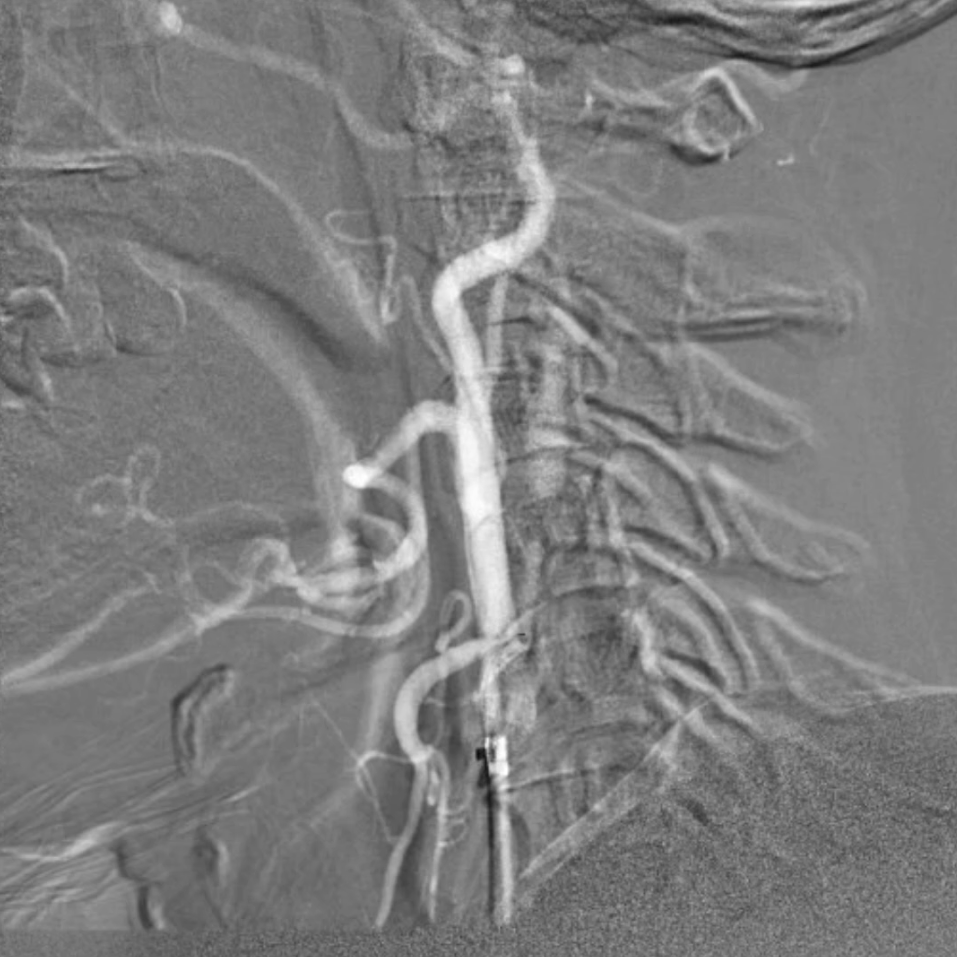

血供改善与安全性验证

造影显示:支架膨胀良好,无需后扩张;

颅内血供:左侧颈内动脉血流通畅,因右侧闭塞,左侧成为全脑主要供血通路,血供恢复满意